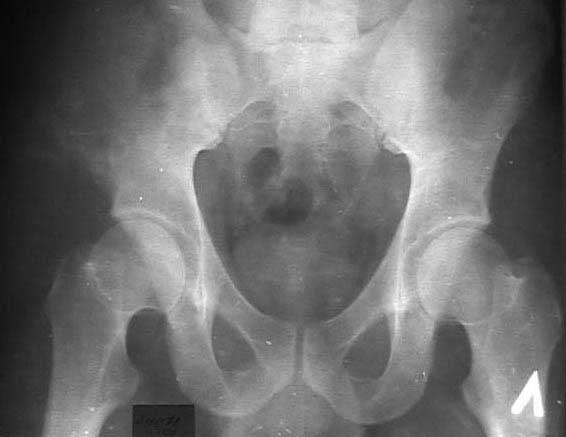

В 2002 году буквально "промелькнул" и исчез пациент с подобным остеолизом. Обследован (биопсия ) в отделении костной онкологии, а затем у дерматологов. Причиной остеолиза признан актиномикоз. К сожалению в то время не удалось выполнить КТ, а рентгенограммы не качественные - в приложении.